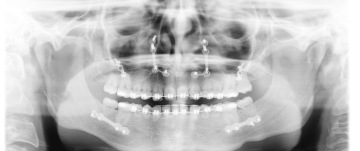

Jako u spoustě dětí se občas stane, že zkrátka zuby nejsou tam, kde by měly být a ani na svá místa zcela nesměřují. Tímto případem jsme byla i já. Avšak, záhy se zjistilo, že to nebude jen tak. Po prvním RTG bylo jasné, že to, co začalo obyčejným předkusem a mezerou mezi zuby, bude mít vážnější dopad.

"Vaše dcera nemá kořeny zubů," zaznělo z úst zubního lékaře. Ano, opět čtete správně. Nemám kořeny zubů (můžete vidět na obrázku z RTG). A tím započala má zdlouhavá ortodontistická léčba fixním aparátem a ten mi v podstatě zůstal do dnes.

Někdy kolem 19 let jsem absolvovala genetické testy, které ukázaly, že resorbce kořenů zubů, tedy jejich ztráta, je geneticky nastavená. Jedná se tedy o neznámou genetickou anomálii.